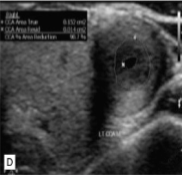

This was seen at the patient’s aorta.

How does it appear sonographically?

What pathology can be assumed here?

Inflamed arterial walls (thickened and narrow)

Takayasu’s Arteritis